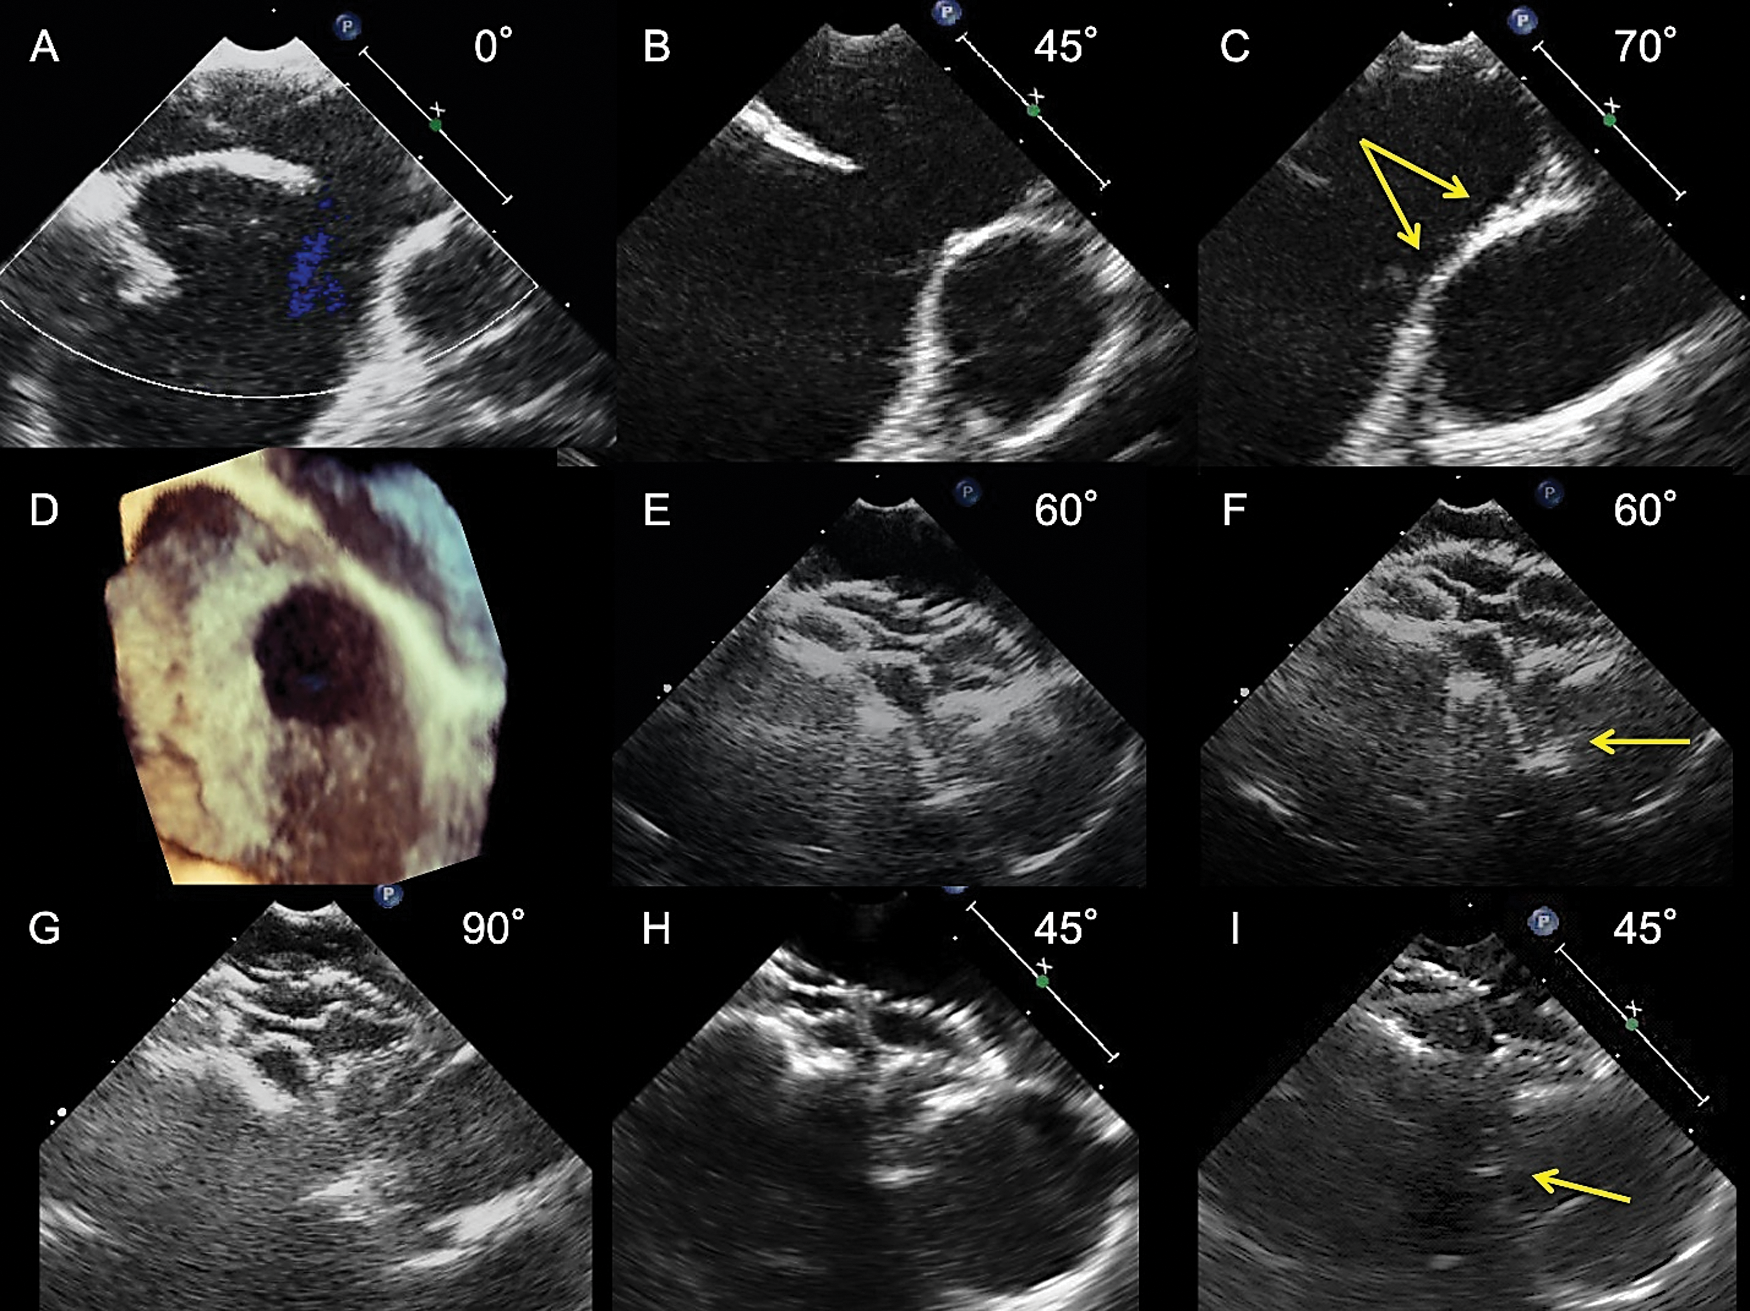

Images Congenital Heart Disease Images Doi 10 Chd 21 Article Efficacy And Safety Of The Atrial Septal Defect Closure For Patients With Absent Or Malaligned Aortic Rim Using A Figulla Flex Ii Device Flared And Straddling Behind The